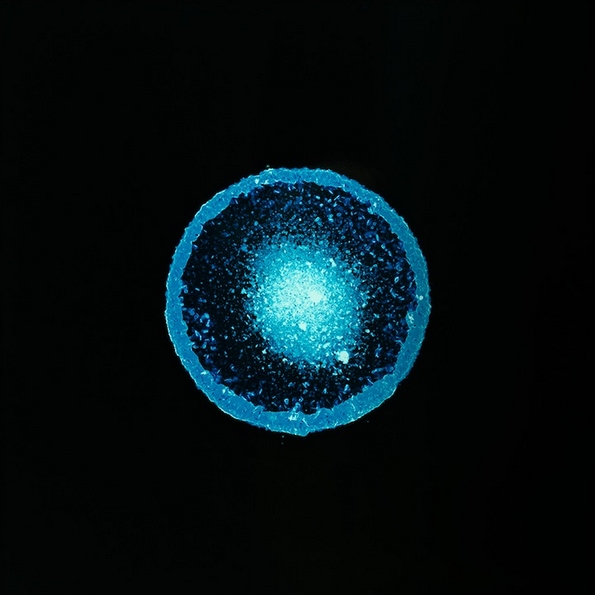

Кристален метамфетамин

Па така, решила да го спроведе овој проект и успеала да направи одлични фотографии. Таа капнала по неколку капки од различни илегални и легални дроги на филм за апарат кој претходно бил осветлен. Во реакција со филмот, супстанците се зголемиле и рашириле во аморфни форми и живописни бои, што резултирало со одлични фотографии. Таа ја нарекла серијата фотографии „All You Can Feel“.